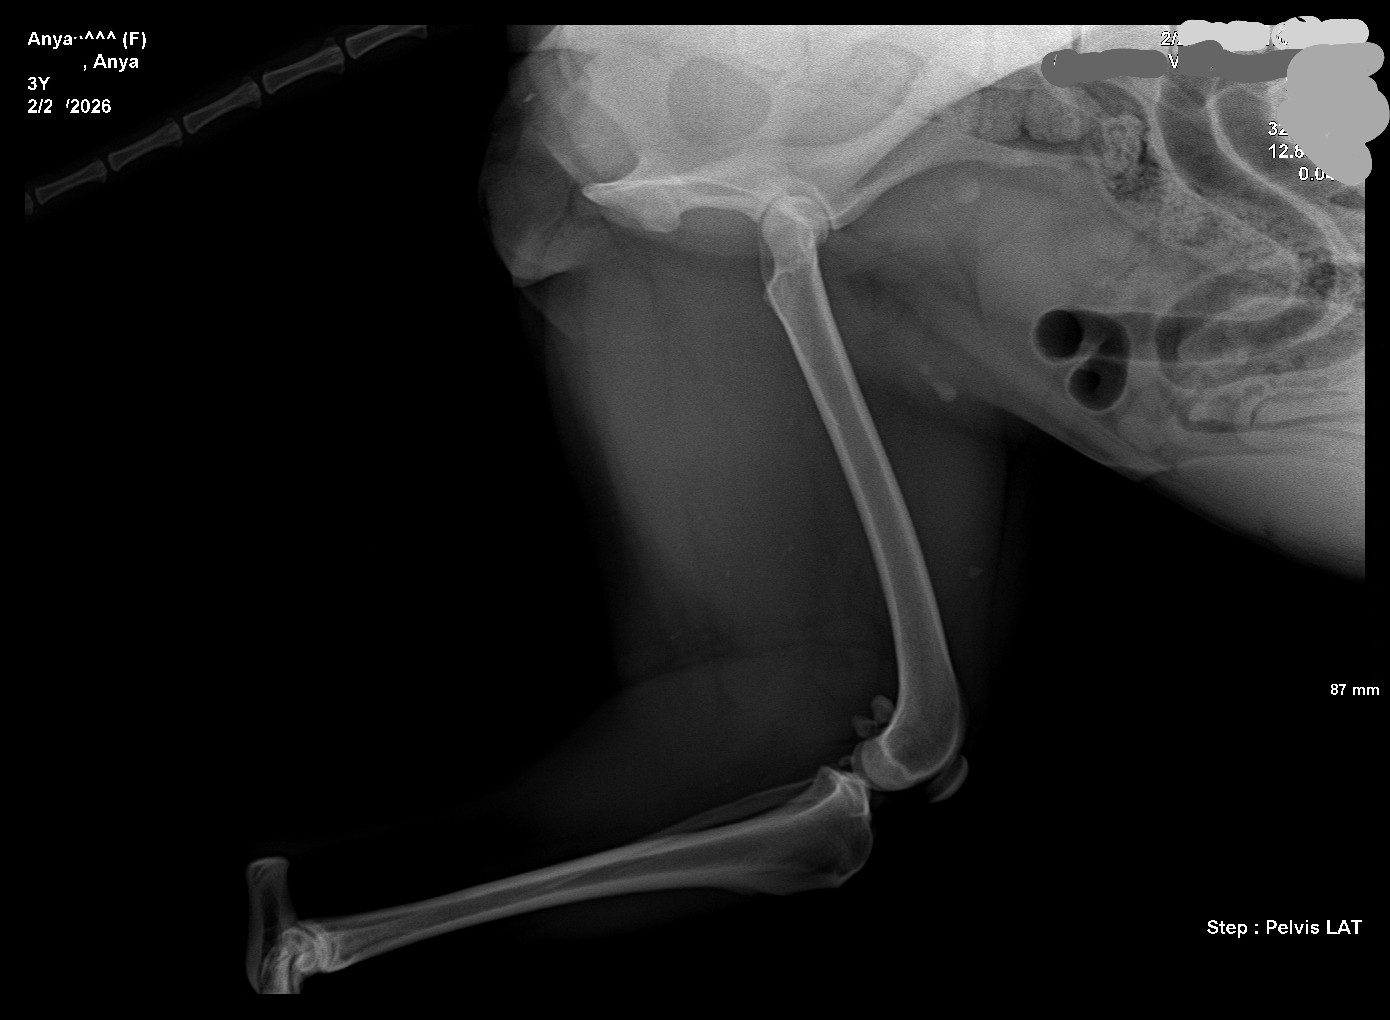

I'm one step closer to breeding Anya. The vet says she has good hips.

>>5107505What are you talking about? I want her to have little babies some day. All the professionals x-ray dog hips.